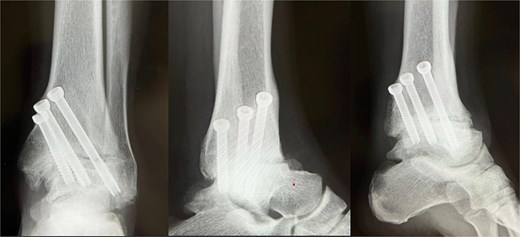

At 1.5 years, hardware removal was performed, with imaging confirming solid osseous union (Fig. 5). The Japanese Orthopaedic Association (JOA) score improved from 56.0 preoperatively to 81.4 at one year and 84.7 at the final 6.5-year follow-up. She resumed 60–70 matches per year without ankle pain, swelling, or motion-related discomfort. Her retirement after 6.5 years was unrelated to the ankle, resulting instead from cervical spine trauma and bilateral knee degeneration. Throughout follow-up, she remained free of ankle-related complications or functional restrictions.

Plain radiograph after hardware removal. At 1.5 years after surgery, the patient underwent hardware removal. Although the osteoarthritic changes in the subtalar joint have slightly progressed, radiographic evaluation confirmed solid osseous union at the tibiotalar joint.